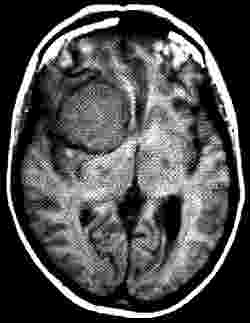

Herpes-Encephalitis. Erhöhtes Signal vor allem im linken Temporallappen. Sicht von vorn.

Aus: Lissner, J., Seiderer, M. (1990)